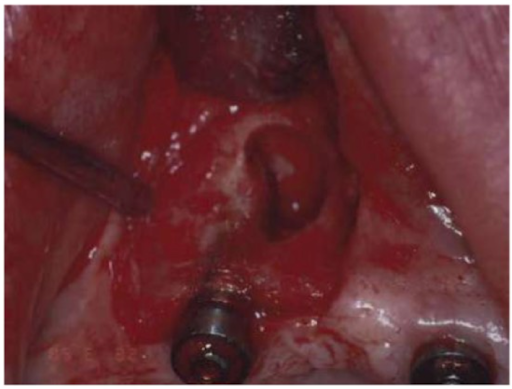

Việc kiểm soát tốt các biến chứng và di chứng phẫu thuật Implant góp phần rất lớn vào quá trình thành công của Implant và tăng tuổi thọ của loại phục hình trên bệnh nhân. Bài viết khái quát các biến chứng và di chứng phổ biến thường gặp, giúp Nha sĩ có cái nhìn tổng quát nhất đối với phẫu thuật Implant. Cùng tìm hiểu.